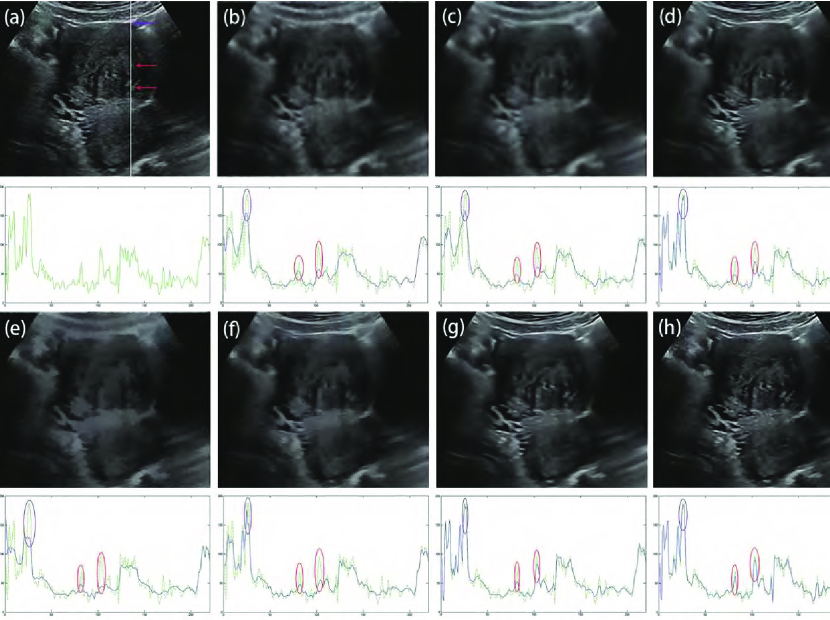

The parameter is an important parameter that is related to the noise level estimation. Noise level estimation is a prerequisite for various detail-preserving image denoising methods [21] but has remained as an unsolved challenging problem in ultrasound image despeckling. According to (16), if is set to a large value, a large diffusion coefficient is obtained that will cause some details to be damaged after speckle reduction. However, if is set to a small value, a small diffusion coefficient is achieved that will increase computational costs in the despeckling process. To explore the impact of parameter , we set with different values. Fig. 4 depicts the despeckled results of different . It is observed that there is a significant level of noise in the despeckled result of . As indicated by the red arrow in Fig. 4(d), the meaningful detail is damaged after noise removal in the case of . Our method achieves not only satisfactory feature preservation but also desirable noise reduction in the case of . In real image experiments, we find that the best range of is from to . Here, we set as .

The parameter is the iteration number. We integrate into the diffusion coefficient, as shown in (16). If is set to a large number, a small diffusion coefficient will be obtained. This strategy will overcome the problem inherent in the traditional AD model that tends to decrease the edge feature contrast as increases. Fig. 5 depicts the despeckled results of different . In the case of , our filter has removed the speckle noise while preserving features properly. As the increases, features are all effectively protected to the same extent. To reduce the required time for despeckling, we set .

To more closely evaluate despeckled images of different filters, we adopted the method in [69] which evaluates all the features located in a single scan line through the ultrasound image. Fig. 8 shows the despeckled images of different filters and their corresponding intensity value profile at the same scan line (marked as white solid line across the image in Fig. 8(a)). The intensity profile of scan line shows that, Frost, SRAD, SBF and ADLG all fail to maintain the edge contrast, reducing the visual effect. OBNLM and NLLRF succeed in enhancing the high-contrast edges in regions of interest (ROI) shown by the purple window. For low-contrast edges indicated by the red windows, both the OBNLM and NLLRF methods fail to preserve the local contrast of edge. As shown by the ROI in red windows in Fig. 8(h), after edge enhancement using adaptive fractional-order , there are slight differences of edge contrast between the despeckled image of the PFDTV method and the original ultrasound image. Compared with other filters, the PFDTV method achieves the best performance in preserving the edge contrast. More despeckled results are depicted in Fig. 9. Obviously, the PFDTV method removes speckle noise thoroughly while preserving features satisfactorily.